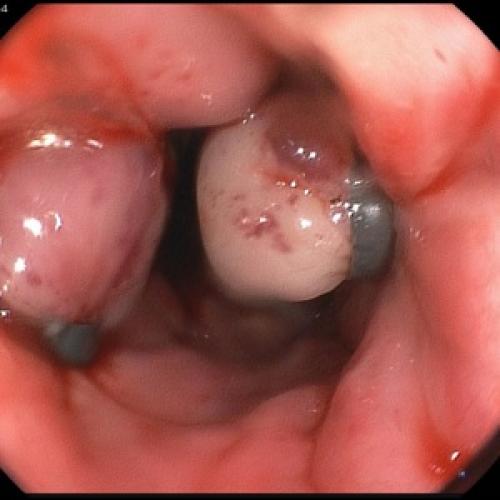

Пациентам с предположительным клиническим диагнозом острого панкреатита показано выполнение ЭГДС (дифференциальный диагноз с язвенным поражением гастродуоденальной зоны, осмотр БДС).

Отсутствие эффекта от проводимой анальгетической и спазмолитической терапии в течение 12-48 часов, быстро прогрессирующая желтуха, отсутствие желчи в ДПК при ЭГДС, признаки билиарной гипертензии по данным УЗИ свидетельствуют о стеноза терминального отдела холедоха (вклиненный конкремент БДС, папиллит). В этом случае показано проведение ЭПСТ. При остром панкреатите ЭПСТ производится без ЭРХПГ!